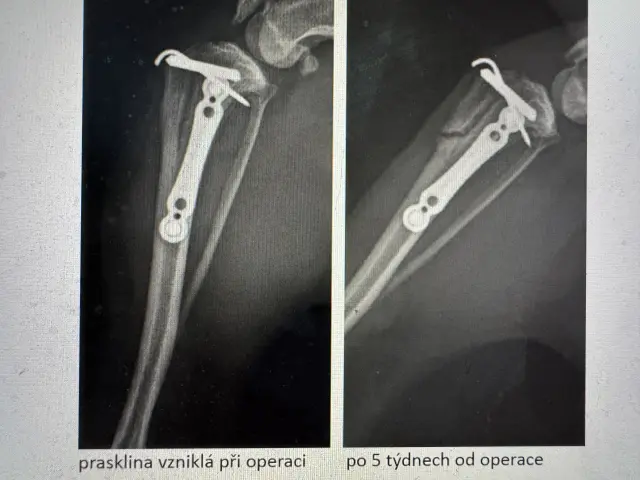

Po operaci druhé zadní nožičky se objevily komplikace – kontrolní RTG odhalilo frakturu kortexu (zlomenina namáhaného místa).

Po vyžádání RTG ze dne operace jsme zjistili, že fraktura se stala během zákroku, o čemž nám pan doktor neřekl. Díky prasklině musela být Willíčkovi navíc zavedena fixační destička s hřebem, nikoliv skrze prevenci, jak nám bylo nepravdivě sděleno.

Prasklina pracovala a bohužel praskla dál, viz snímek níže.